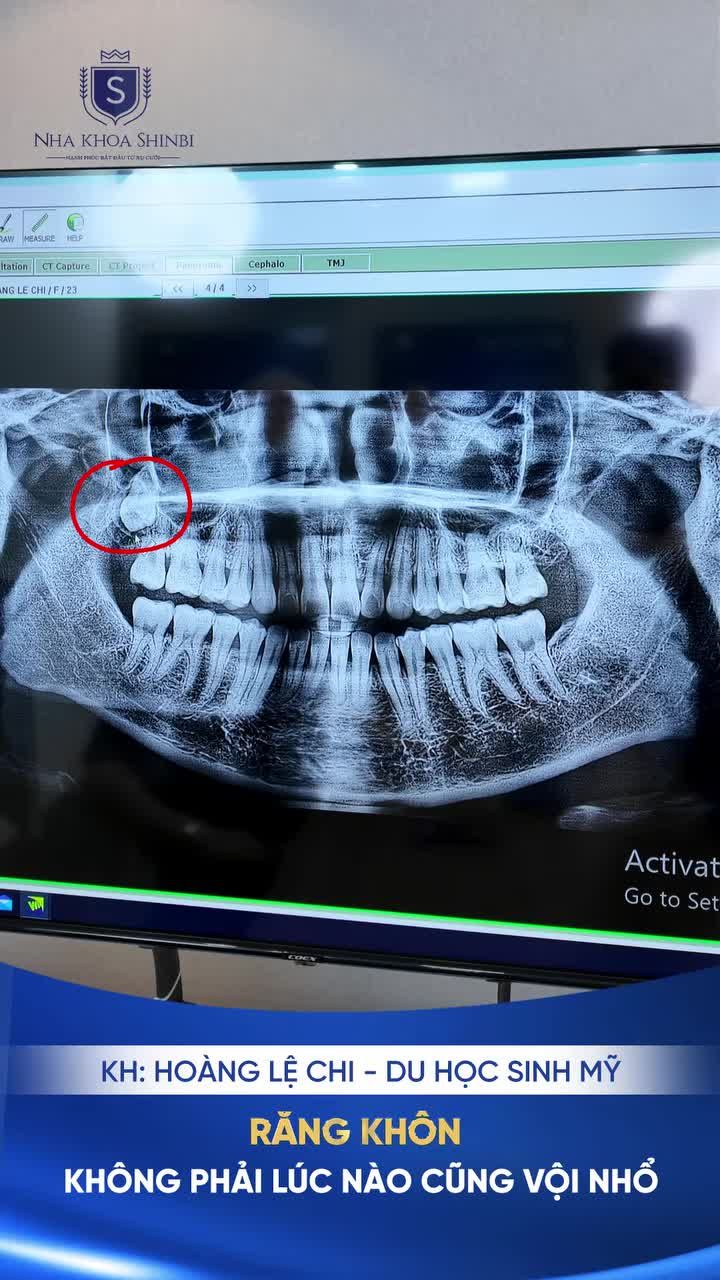

"RĂNG KHÔN KHÔNG PHẢI LÚC NÀO CŨNG "VỘI" NHỔ "

6 ngày trước

·

20 Lượt xem